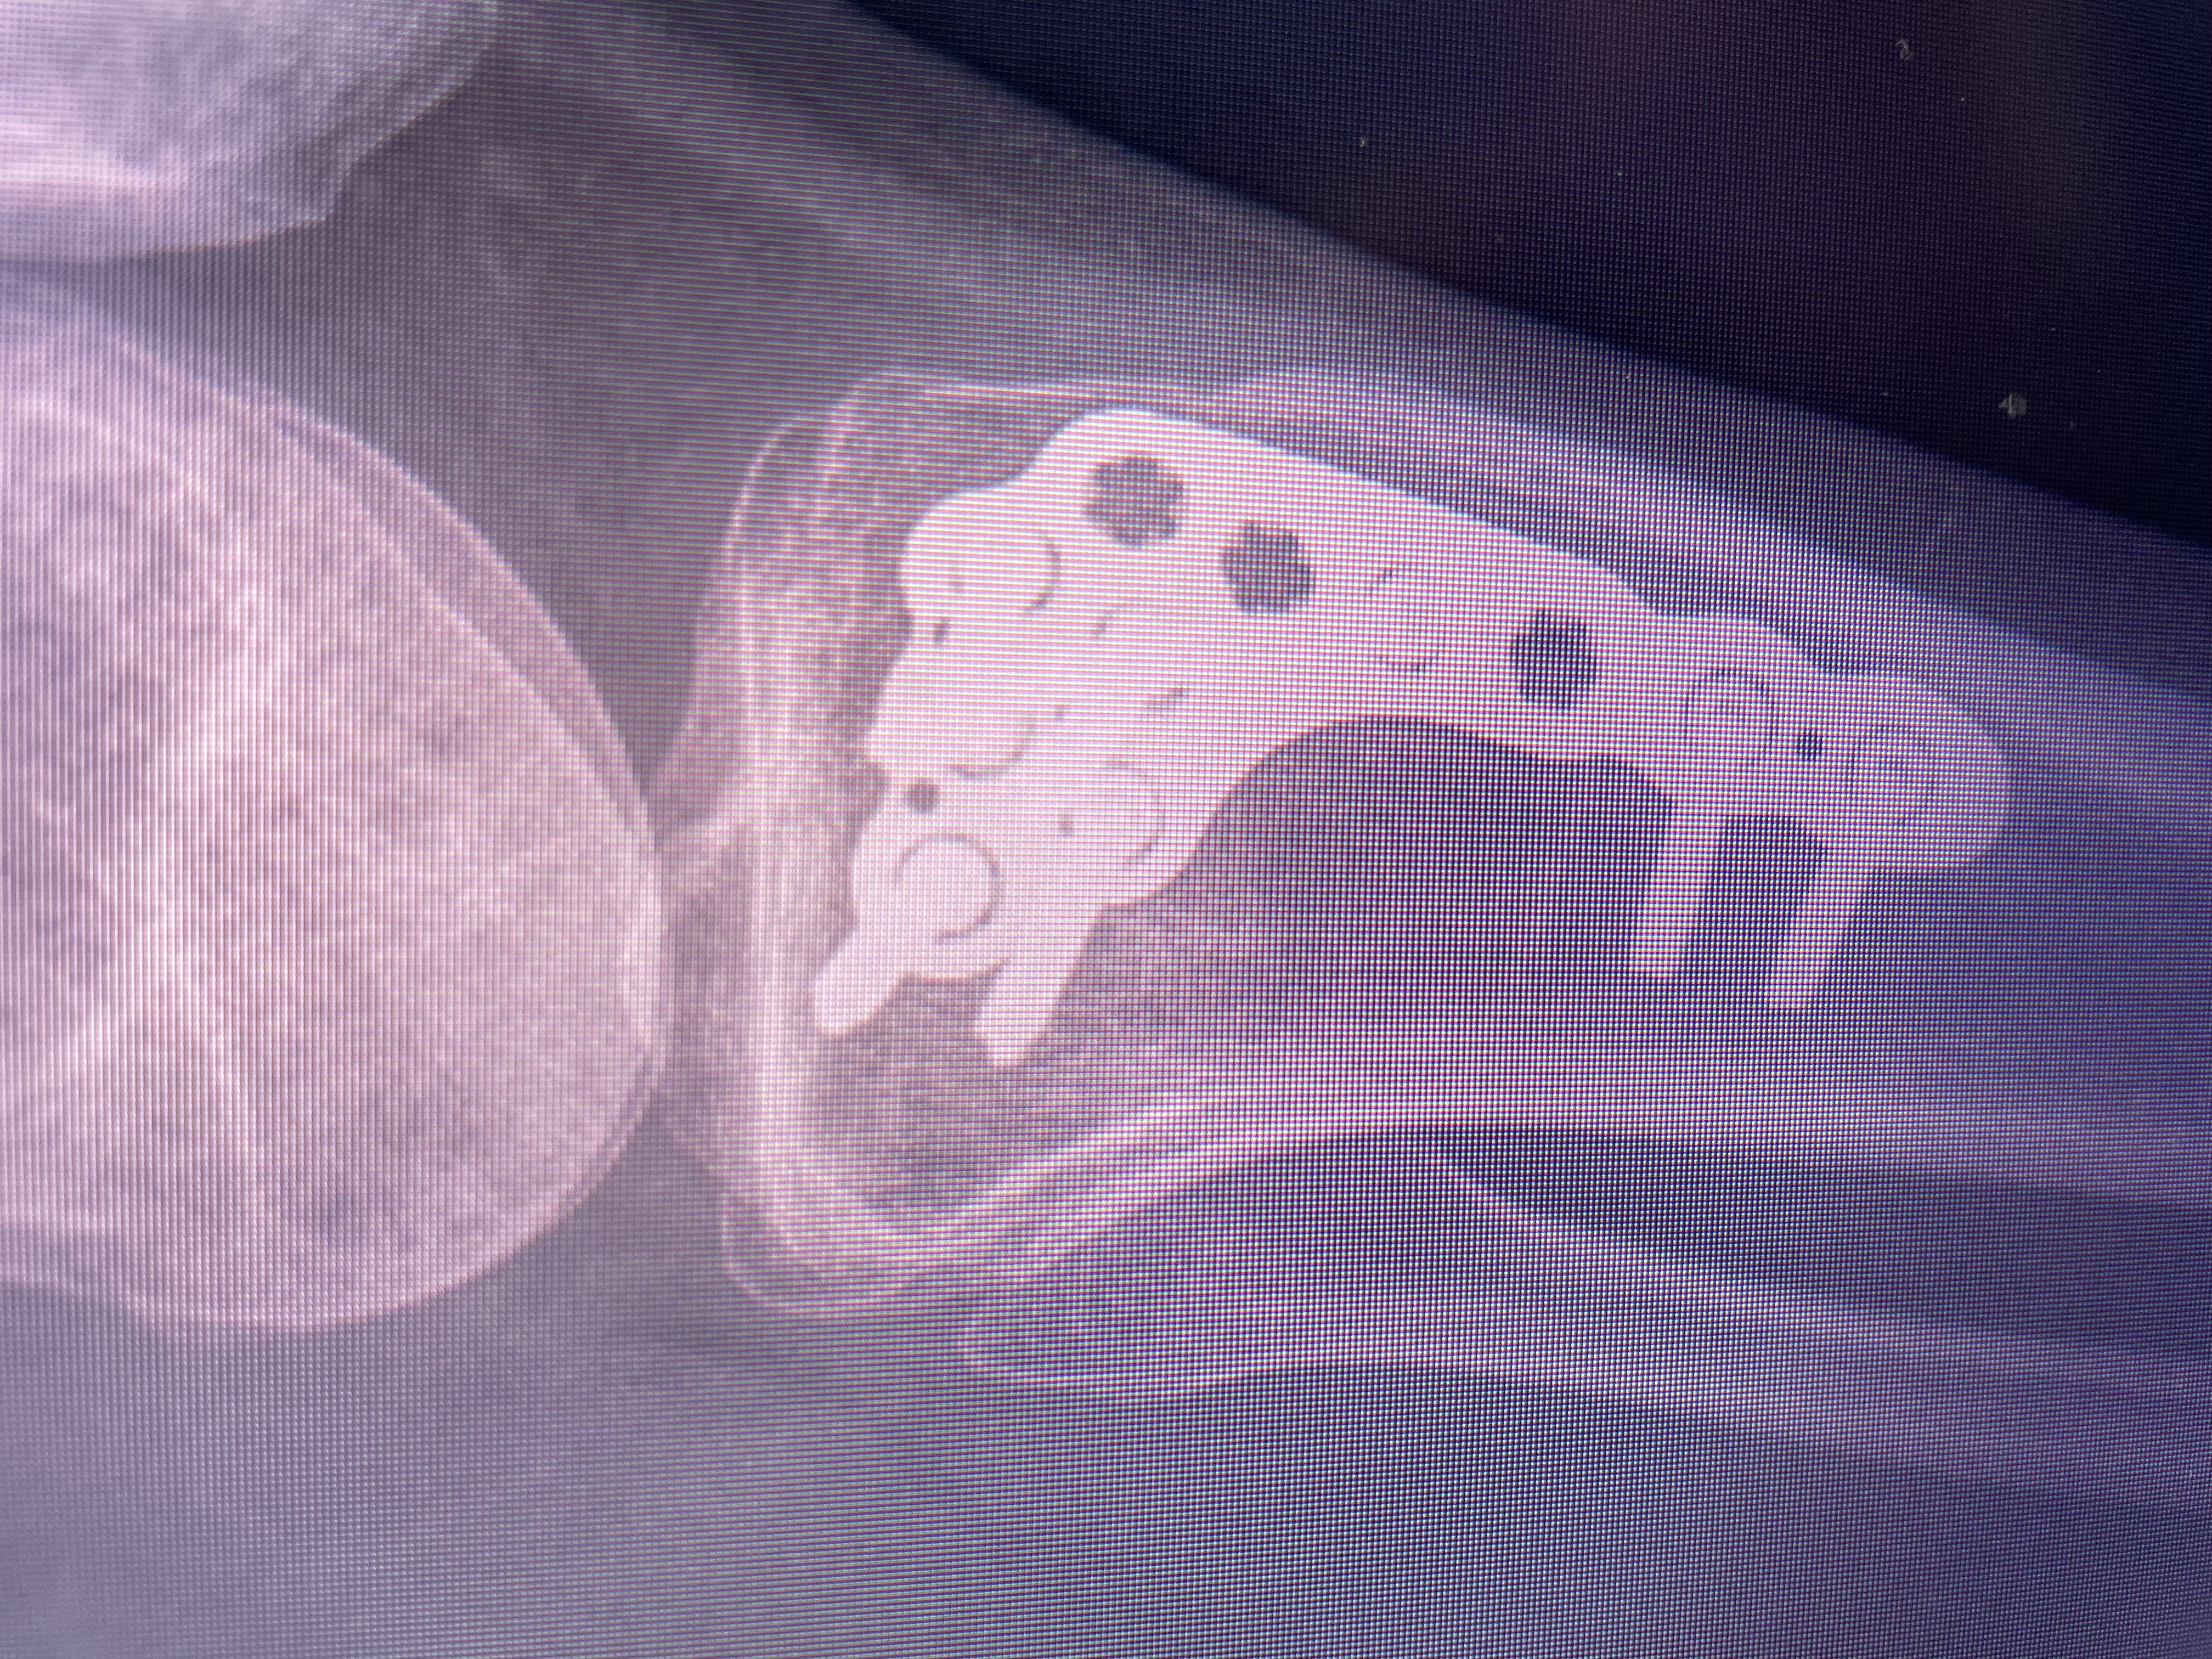

Last May, while I was out dog walking (my job and absolute passion!), one of my clients’ dogs accidentally crashed full speed into my leg. The impact was so strong it fractured my left tibia. I needed orthopaedic surgery to repair the break, and I now have a large metal plate and 8 screws holding my leg together.

Recovery hasn’t been easy. I’ve done everything I can to heal and get back to normal, but the metal hardware has been causing ongoing pain, discomfort, and limited mobility. My doctor has said I’m now eligible to have the plate and screws removed (YAY) — something I’ve been looking forward to for months.